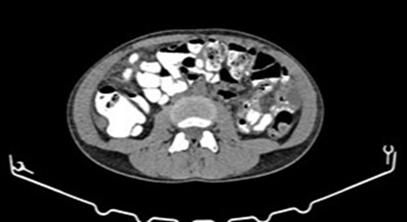

patient exhibited remarkable treatment response on follow-up ct scans, with a

regression of ascitic fluid and a decrease in the size of the mass in the

lesser pelvis to 3.5 x 2.5 cm, as well as of the concomitant lesions in the

paracolic gutters and the omentum (figure 3). Subsequently, the patient

Figure 3: post-chemotherapy contrast enhanced ct scan for

tumour response assessment